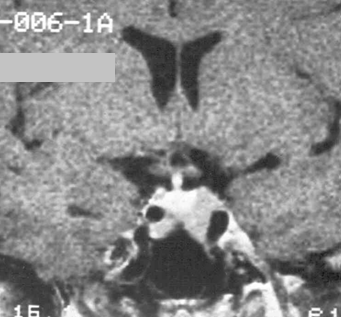

The analysis of the sellar floor can be done with CT, if possible in the coronal plane.

Signal change on MRI in pituitary adenomas:

Microadenomas on T1WIs appear with much lower signal intensity compared to white matter, while compared to the grey matter they are only less intense.

On T2 weighted images they show great variability. They can be bright, isointense and hypointense as well.

Macroadenomas can show necrobiotic phenomena, thus due to hemorrhage and cystic degeneration their signal is inhomogeneous, especially on T2 weighted sequences. However homogenous macroadenomas can also be seen.